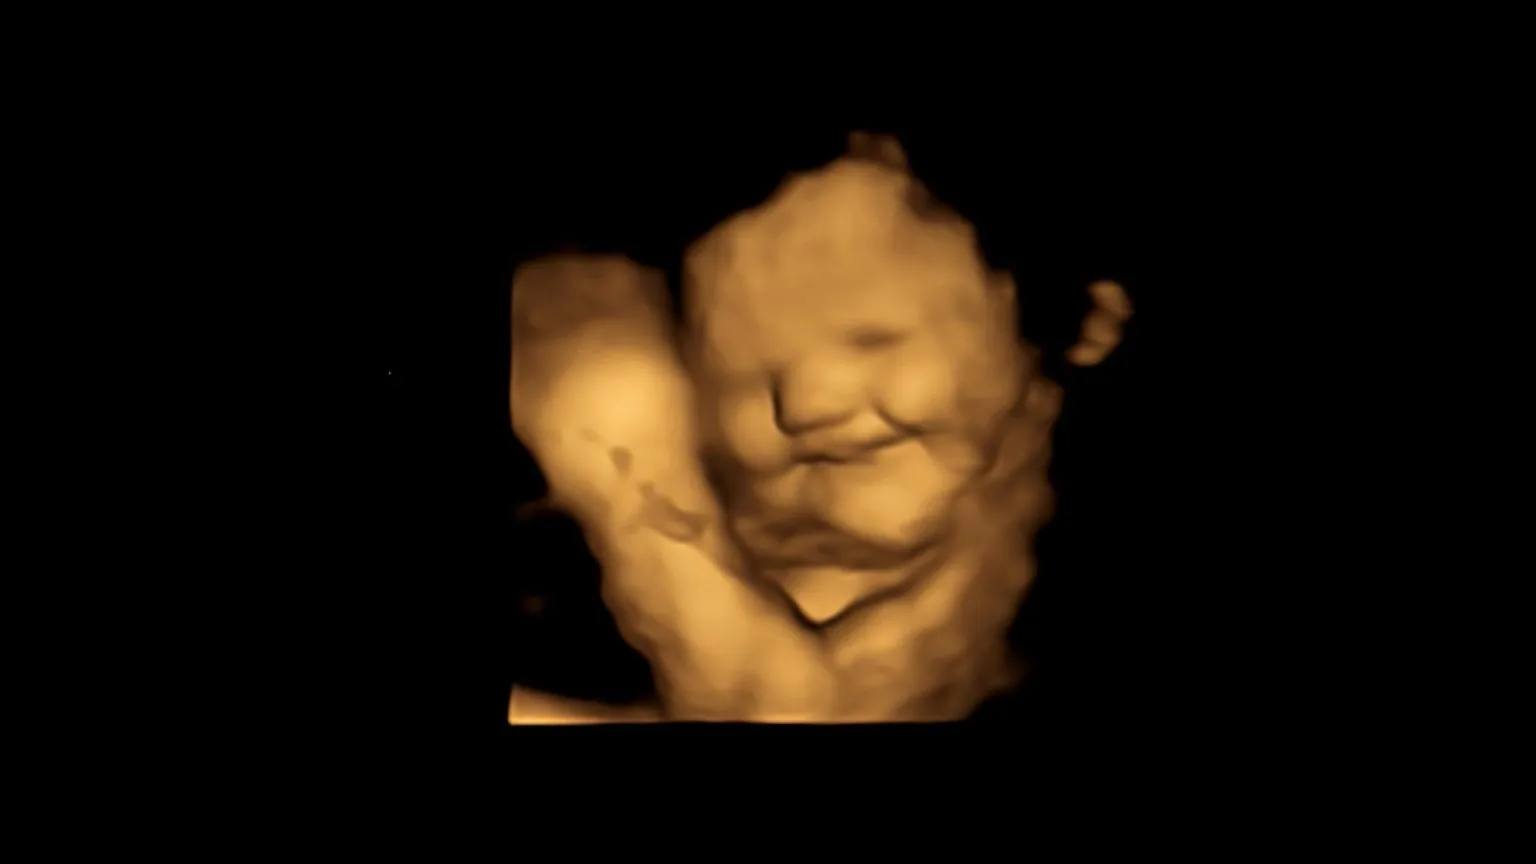

首席研究员Beyza Ustun,达勒姆大学心理学系胎儿和新生儿研究实验室的研究生,说。"一些研究表明,婴儿在子宫内可以品尝和闻到气味,但它们是基于出生后的结果,而我们的研究是第一个在出生前看到这些反应的研究。"

她继续说:"因此,我们认为,在出生前反复接触各种味道可能有助于建立出生后的食物偏好,这在考虑围绕健康饮食的信息传递以及在断奶时的食物选择时可能很重要。在扫描过程中看到未出生的婴儿对甘蓝或胡萝卜口味的反应,并与他们的父母分享这些时刻,这真的很令人惊讶。"

研究小组包括来自英国伯明翰阿斯顿大学和法国勃艮第大学国家科学研究中心的专家,他们在怀孕32周和36周时对年龄从18岁到40岁的妇女进行扫描,以检测胎儿对甘蓝和胡萝卜口味的面部反应。

与未接触任何一种味道的对照组中的胎儿相比,在这两种味道组中看到的面部反应表明,仅仅接触少量的胡萝卜或甘蓝味道就足以刺激反应。

共同作者、达勒姆大学心理学系胎儿和新生儿研究实验室主任Nadja Reissland教授监督了Beyza Ustun的研究。她说。"以前在我的实验室进行的研究表明,4D超声扫描是监测胎儿反应的一种方式,以了解他们对母亲健康行为(如吸烟)的反应,以及他们的心理健康,包括压力、抑郁和焦虑,这项最新研究可能对了解胎儿感知和分辨母亲摄入的食物的不同味道和气味的能力的最早证据有重要意义。"